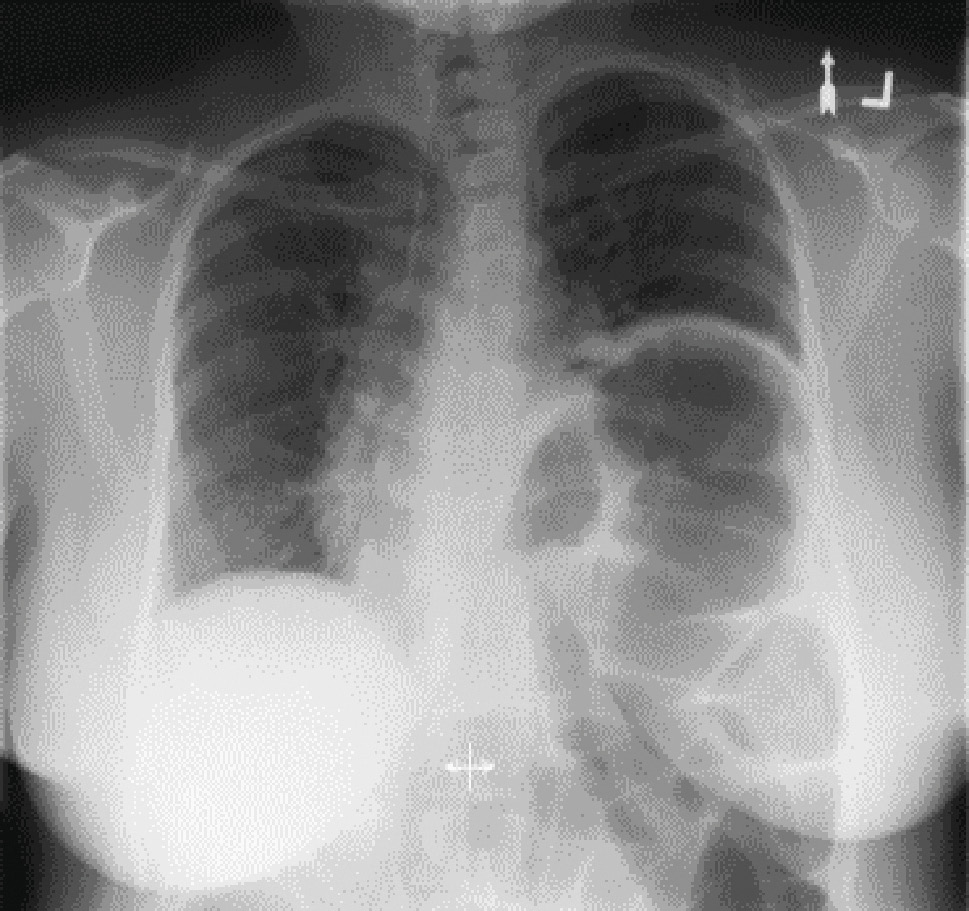

3.2.1. Рентгеноскопия и Sniff-тест

Рентгеноскопия во время глубокого дыхания позволяет оценить расположение и экскурсию диафрагмы. Проведение так называемого sniff-теста (резкий вдох через нос с имитацией нюхательного движения) является традиционной методологией, используемой для диагностики одностороннего паралича диафрагмы. Во время нюхательного маневра у пациентов с односторонним параличом диафрагмы здоровая половина диафрагмы опускается, в то время как пораженная половина совершает парадоксальное движение вверх. При подъеме половины диафрагмы на резком вдохе на 2 см и более тест считается положительным. Однако данный тест имеет ряд ограничений: он не очень специфичен (у 6 % здоровых людей тест положителен), более того, в 20 % случаев тест положителен при двустороннем поражении диафрагмы. У пациентов с двусторонней слабостью диафрагмы тест также может быть ложноотрицательным за счет расслабления мышц брюшной стенки в начале вдоха. В этом случае диафрагма опускается за счет смещения передней брюшной стенки наружу [23, 24] (рис. 3).

Рис. 3. Рентгенограмма грудной клетки в прямой проекции больного с хроническим подъемом левой половины диафрагмы неизвестной этиологии [23]

Fig. 3. Posterior-anterior projection upright chest radiograph of the patient with chronic left hemidiaphragm elevation from unknown etiology [23]